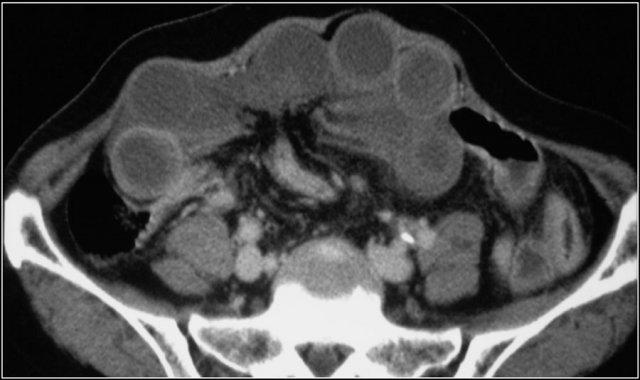

Ruột Sốc

Ở bệnh nhân sốc giảm thể tích, có sự phân phối lại dòng máu.

Điều này có thể dẫn đến hình ảnh ngấm thuốc mạnh bất thường của thành ruột, như trong trường hợp bệnh nhân đang trong tình trạng sốc mất máu này.

Lưu ý một số quai ruột có kiểu hình tăng tỷ trọng (dạng trắng), trong khi các quai khác lại có dấu hiệu bia nước.

Hình ảnh tĩnh mạch chủ dưới dạng khe hẹp là do tình trạng giảm thể tích tuần hoàn (mũi tên đỏ).

Do hệ quả của sự phân phối lại dòng máu ưu tiên đến các cơ quan thiết yếu, những bệnh nhân này có thể có hình ảnh tuyến thượng thận ngấm thuốc quá mức, vì các cơ quan này cần tăng cường sản xuất adrenaline để đáp ứng với tình trạng sốc.